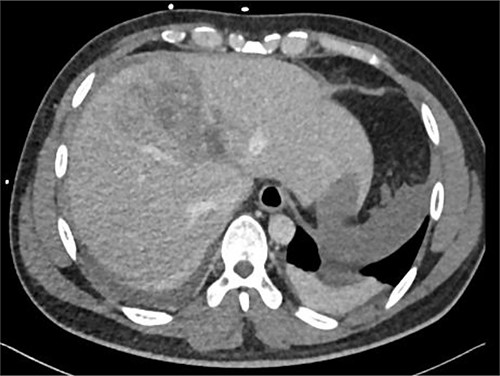

After 1 week of embolization, a follow-up CT scan detected thrombosis of the lateral segmental branch of the left portal vein. Prophylaxis dose of heparin was increased to the therapeutic range and, a week later, duplex US examination was performed, which documented the resolution of this thrombosis. The patient was transferred to the rehabilitation care on daily oral aspirin. A repeat CT scan was done after 1 month in which no pseudoaneurysm was seen, with normal flow in the hepatic arteries and portal vein (Fig. 7). During the following 2 months, the patient remained asymptomatic and was discharged home without complications.

Repeated CT scan of the abdomen after 4 weeks revealed partial healing of the liver injury with disappearance of the pseudoaneurysm.